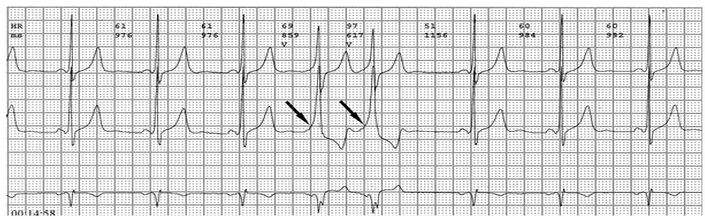

各旁路引起预激的心电图特征如下:

1、房室旁道

(1)PR间期(实质上是P-δ间期)缩短至0.12秒以下,大多为0.10秒;

(2)QRS时限延长达0.11秒以上;

(3)QRS波群起始部粗钝,与其余部分形成顿挫,即所谓预激;

(4)继发性ST-T波改变。

上述心电图改变尚有分为A、B两型的。A型的预激波和QRS波群在V1导联均向上,而B型V1导联的预激波和QRS波群的主波则均向下;前者提示左室或右室后底部心肌预激,而后者提示右室前侧壁心肌预肌。这种分类方法虽然受到预激是不同部位旁路所致的多变QRS波群的限制,但有助于区别旁路的心室端在左或右、前或后,因而沿用至今。

PR间期正常,QRS波群增宽,有预激波。预激综合征室上性心动过速发作时,预激表现大多消失,心电图表现为QRS波群形态正常的室上性心动过速。并发房扑或房颤时,QRS保持预激特征的不少见,心电图表现为QRS波群畸形宽大的房扑或房颤;心室率大多超过200次/分,甚至可达300次/分。房扑时可呈1:1房室传导,并可能辨认房扑波。房颤时心室律不规则,长间歇之后可见到个别QRS波群形态正常(可能为旁路不应期延长,房室结内隐匿传导作用消失后,冲动全部或大部经房室结传导所致),并可能辨认房颤波。心室率极快时,还可伴有频率依赖性心室内传导改变。

1、典型预激综合征

(1)P-R间期<0.12秒,P波正常;

(2)QRS时间>0.11秒;

(3)QRS波群起始部分变粗钝,称为预激波δ波

(4)继发性ST-TT改变。临床上又分为两型:A型预激:预激波和QRS波群在V1导联向上,其旁道位于左侧房室瓣环周围。B型预激:预激波和QRS波群的主波V1导联向下,在左胸导联V5向上,其旁道位于右侧房室瓣环的周围。